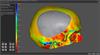

ADEPT screen shot

ADEPT screen shot

An image showing a screen shot from ADEPT software with the thickness view turn on.